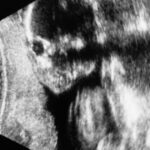

【コラム】リアルタイム6ヶ月。美容師だからこそ確信できる我が子。その模様と感謝と人と…

妊娠6ヶ月の妻をもつ「遅咲きの美容師」です。リアルタイムで妻の妊娠生活を男子目線で綴っています。